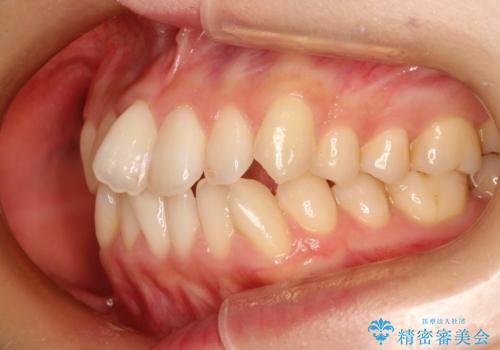

前歯のガタガタをインビザラインで目立たず矯正

- 目立たずに前歯を矯正したいとのことで来院されました。

歯と歯の間にわずかに隙間を作りスペースを確保し、インビザラインにて矯正を行うこととなりました。

前歯の微調整に少し時間がかかりましたが、整った歯並びにすることができました。